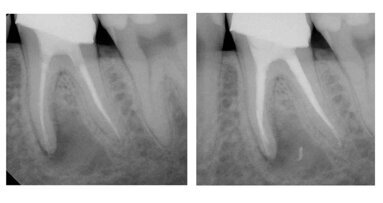

“Does anyone have any advice on how to remove Thermafil with twisted files?” Recently, I received this question via e-mail from a colleague. ...